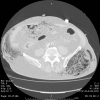

Fig. 4

Bubbles inside the abdomen